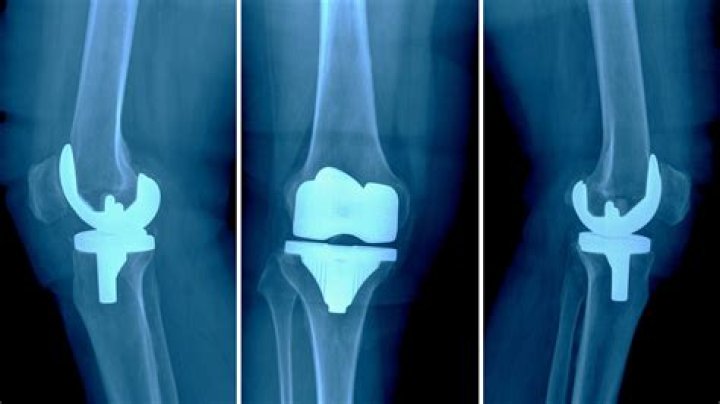

Paul Pogba has decided to go through an operation on his knee as he faces a battle to be really great for this colder season’s World Cup.

The midfielder tore his meniscus not long after returning to Juventus this mid year, but at first chose not to have it worked endlessly doubt looked through out elective prescriptions.

Pogba returned to planning on grass on Monday, but it’s as of now being extensively uncovered that he besieged a wellbeing test and has now decided to finally go through an operation – a hardship responsible to keep him out for something like two months.